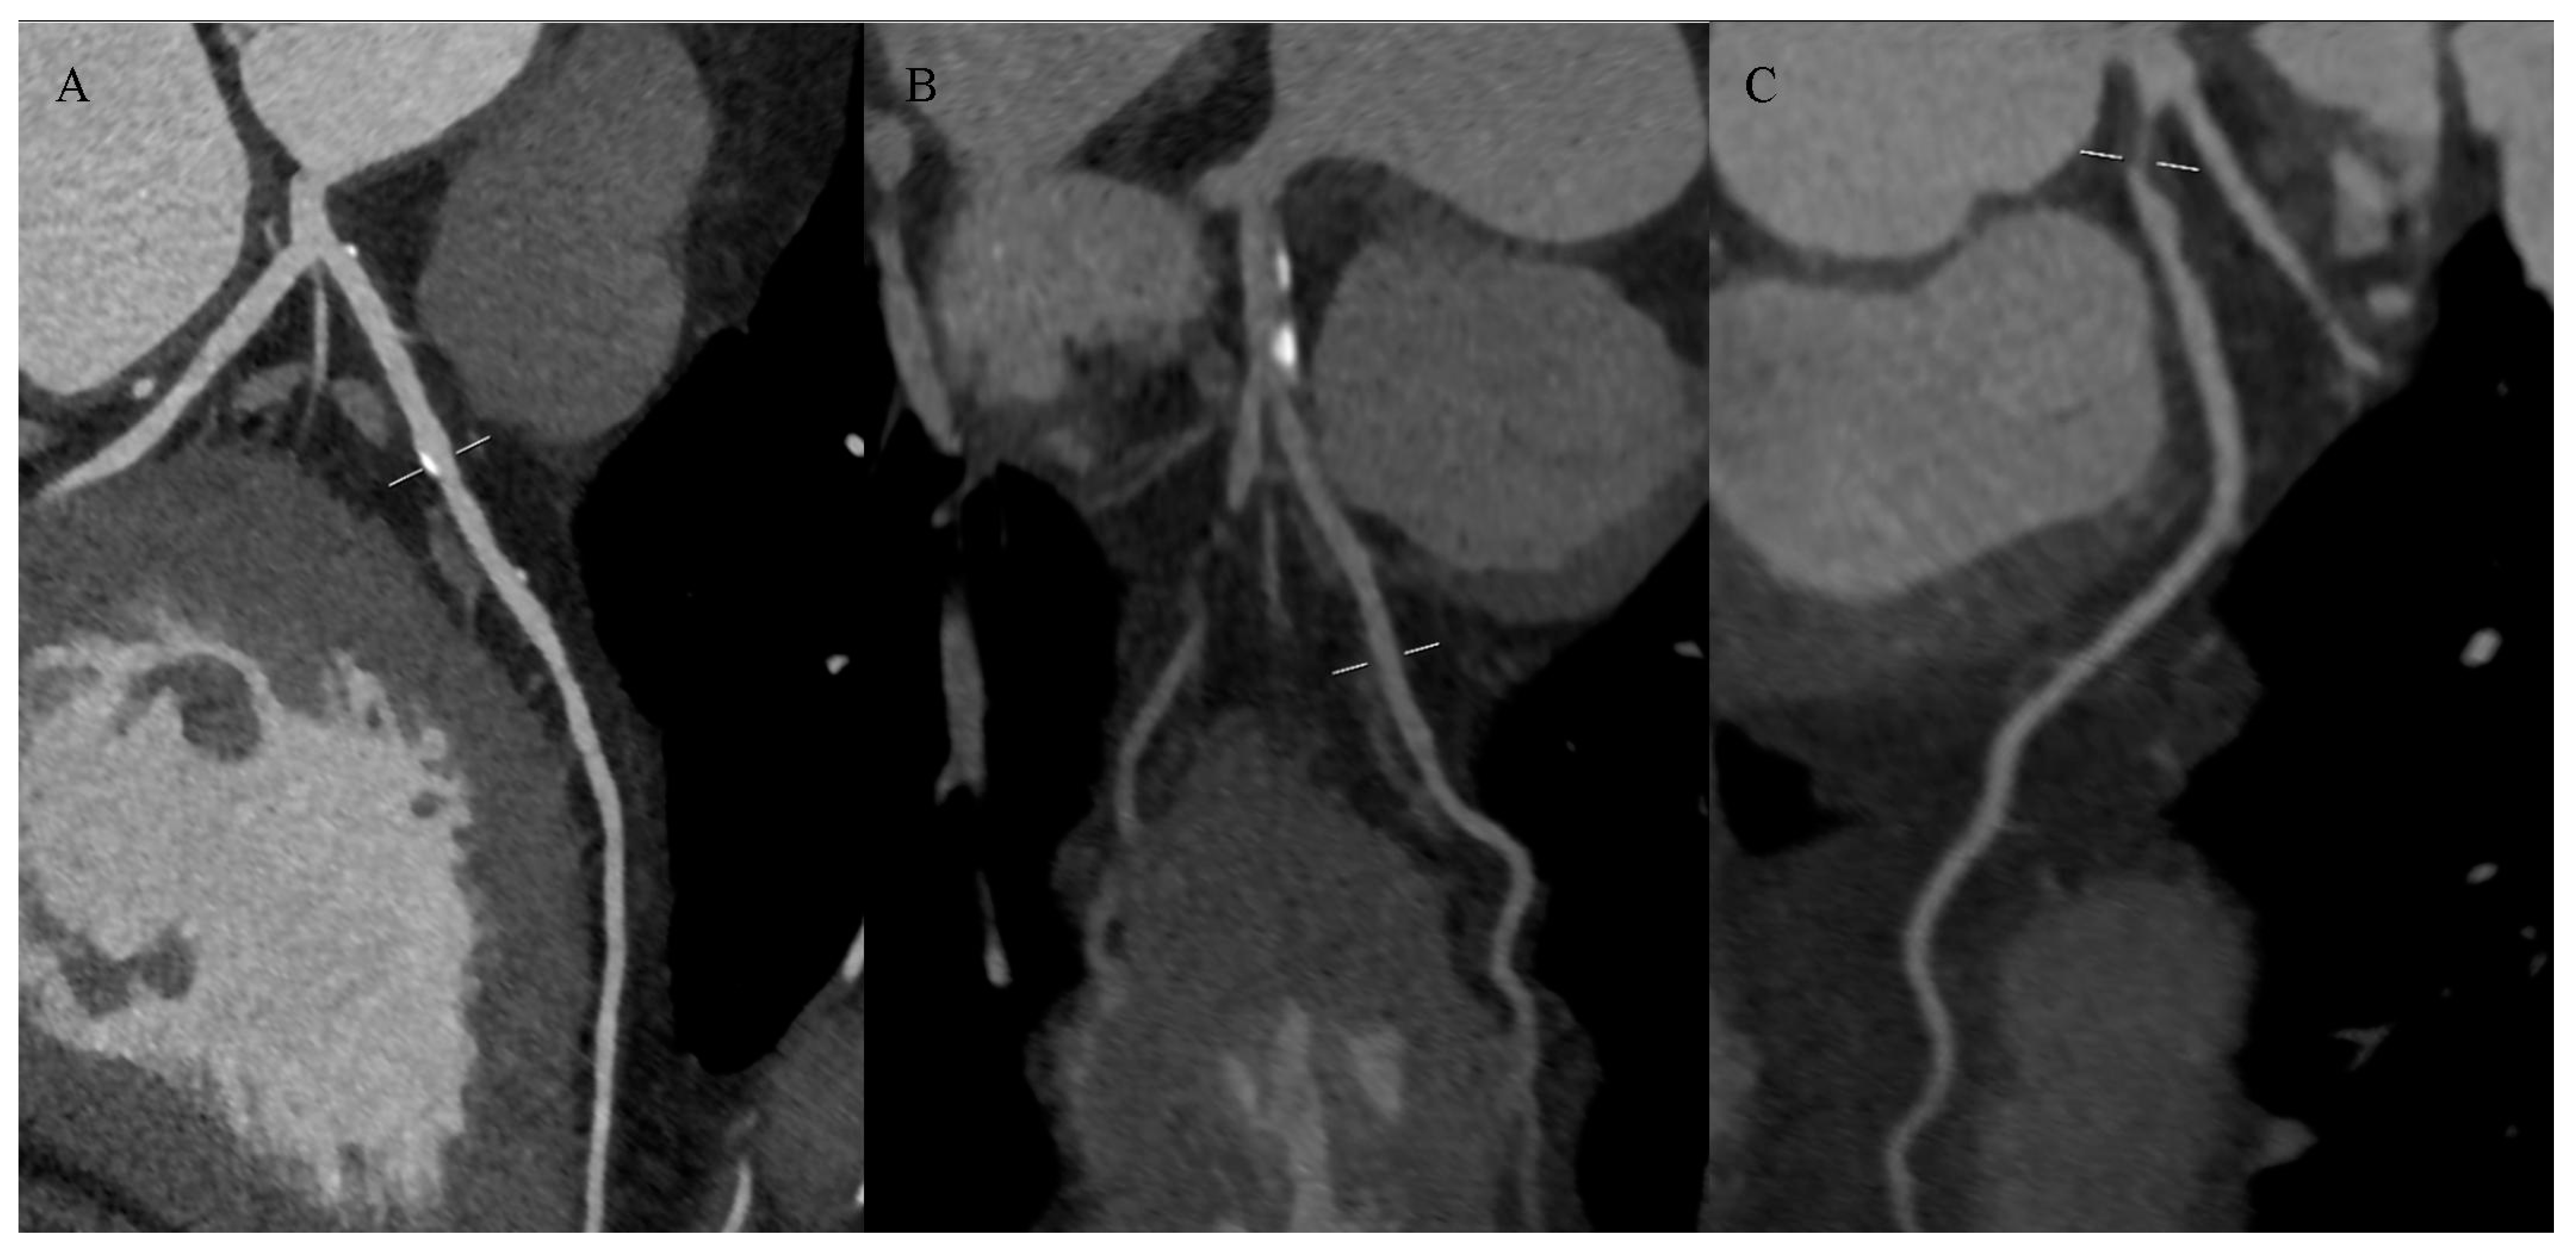

2.4. Computed Tomography Assessment